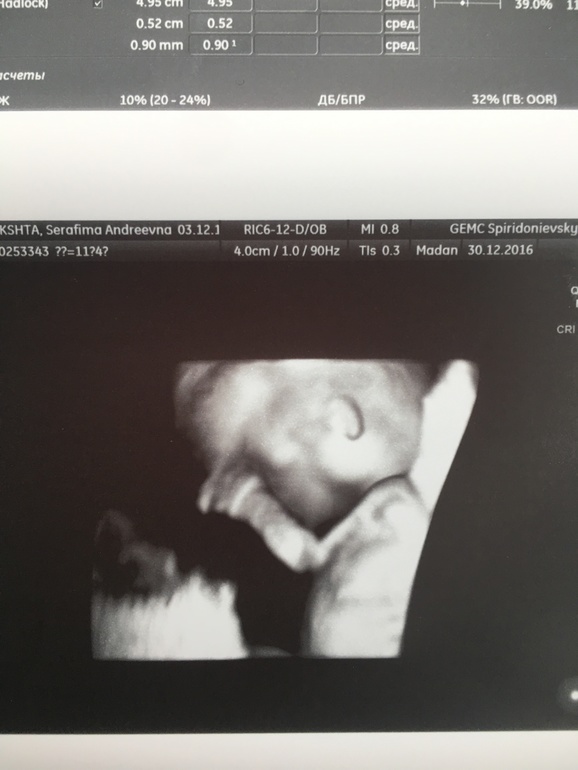

РУЧКА! Пап, дай пять

Я не верю что это со мной! Я будто смотрю фильм про себя!

Я ждала три года этого скрининга)